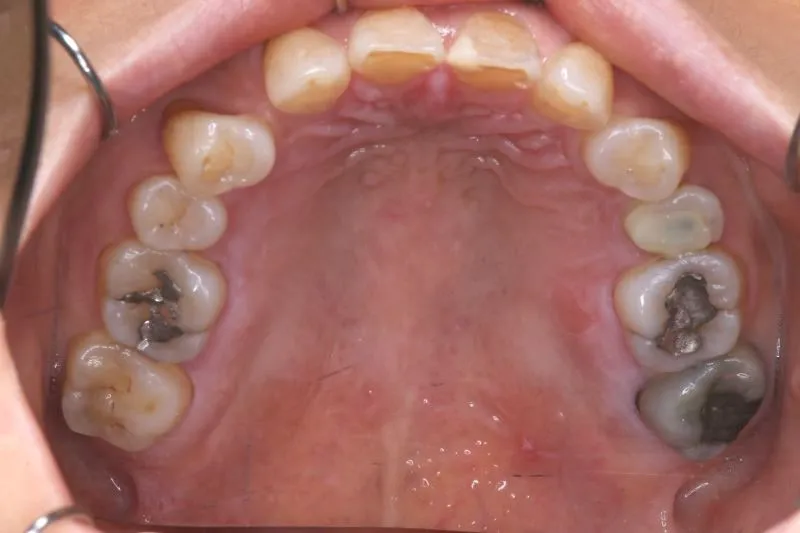

1.主訴 歯が足りない・ガタガタ

2.診断名あるいは主な症状 空隙歯列・先天性欠損歯

上の歯が2本足りないため上下のアーチが合わず、下の歯がガタガタになっています。

上下の幅をあわせ、噛み合わせから調整していきます。